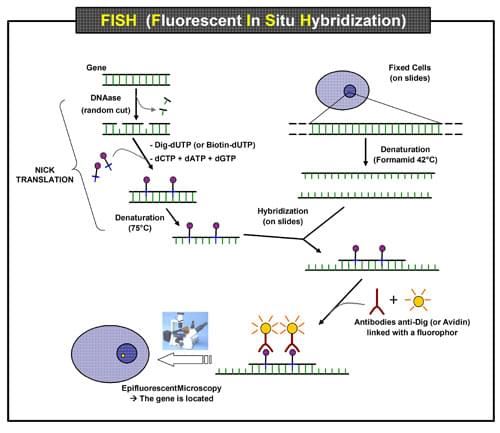

Rys. 1 Schemat zasady eksperymentu FISH mającej na celu lokalizację genu w jądrze.

Rys. 1 Schemat zasady eksperymentu FISH mającej na celu lokalizację genu w jądrze.